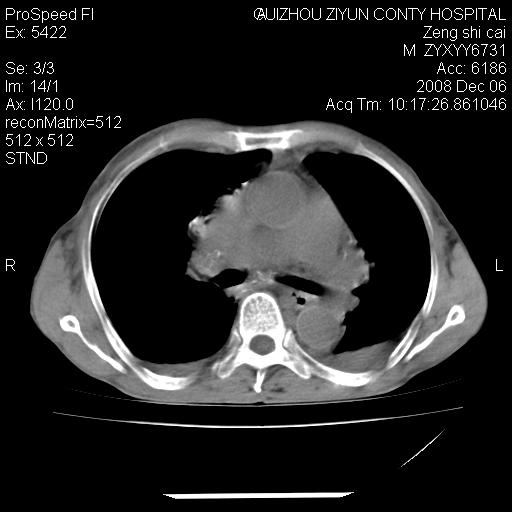

标题: CT16961:M、71岁,咳嗽半年,无血痰;胸片示右肺占位。 [打印本页]

标题: CT16961:M、71岁,咳嗽半年,无血痰;胸片示右肺占位。

右肺癌并纵隔淋巴结及胸膜转移可能性大

右肺癌并纵隔淋巴结及胸膜转移。建议气管镜

右肺纵隔型肺癌伴纵隔淋巴结及胸膜转移!

右肺纵隔型肺癌伴纵隔淋巴结转移!双侧胸水!

1)考虑右肺上叶纵隔型肺癌伴纵隔淋巴结转移。2)心包积液,双侧胸腔积液。

右肺癌并纵隔淋巴转移,腹膜后转移可能性大,两侧胸腔积液

右肺癌并纵隔淋巴结及胸膜心包转移,好多团团点点,看得有点想吐

右肺上叶纵隔型肺癌伴纵隔淋巴结转移。心包积液,双侧胸腔积液。

右肺纵隔型肺癌伴纵隔淋巴结转移!双侧胸水\\心包积液

右肺纵隔型肺癌伴纵隔淋巴结及胸膜转移